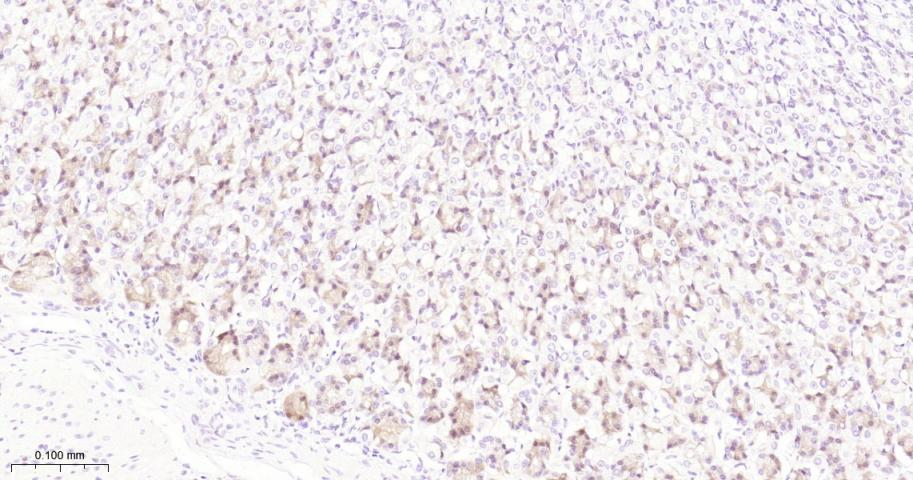

Paraformaldehyde-fixed, paraffin embedded Rat Testicles; Antigen retrieval by boiling in sodium citrate buffer (pH6.0) for 15 min; The section was incubated with RPS6KB1 Monoclonal Antibody, Unconjugated (bsm-62971R) at 1:200 overnight at 4°C, followed by conjugation to the bs-0295G-HRP and DAB (C-0010) staining.

Paraformaldehyde-fixed, paraffin embedded Rat Cerebellum; Antigen retrieval by boiling in sodium citrate buffer (pH6.0) for 15 min; The section was incubated with RPS6KB1 Monoclonal Antibody, Unconjugated (bsm-62971R) at 1:200 overnight at 4°C, followed by conjugation to the bs-0295G-HRP and DAB (C-0010) staining.

Paraformaldehyde-fixed, paraffin embedded Mouse Cerebellum; Antigen retrieval by boiling in sodium citrate buffer (pH6.0) for 15 min; The section was incubated with RPS6KB1 Monoclonal Antibody, Unconjugated (bsm-62971R) at 1:200 overnight at 4°C, followed by conjugation to the bs-0295G-HRP and DAB (C-0010) staining.

Paraformaldehyde-fixed, paraffin embedded Mouse Stomach; Antigen retrieval by boiling in sodium citrate buffer (pH6.0) for 15 min; The section was incubated with RPS6KB1 Monoclonal Antibody, Unconjugated (bsm-62971R) at 1:200 overnight at 4°C, followed by conjugation to the bs-0295G-HRP and DAB (C-0010) staining.